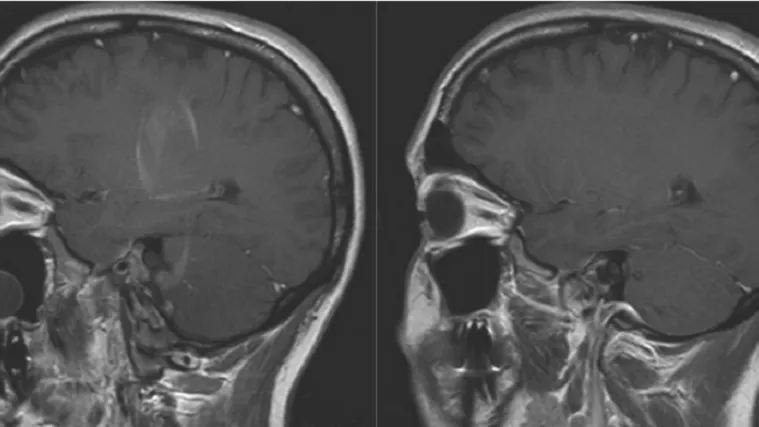

Zika razara i mozak odraslih osoba

Istraživanja su pokazala da zika virus ima razarajući učinak i na neke tipove stanica mozga odraslih osoba, a ne samo na mozak fetusa, objavljeno je u četvrtak u SAD-u.

Prema istraživanju objavljenom u časopisu Cell Stem Cell, taj virus može uništiti stanice odraslih koje se koriste za učenje i pamćenje.

Dok je učinak virusa zika na fetus dokazan, posebice opasnost da izazove mikrocefaliju, to nije slučaj s odraslima.

Stanice u dva dijela mozga pokazale su se posebno osjetljivima na virus, među kojima u hipokampusu.

Znanstvenici su također naglasili da se dugoročni učinci na mozak teško mogu predvidjeti.